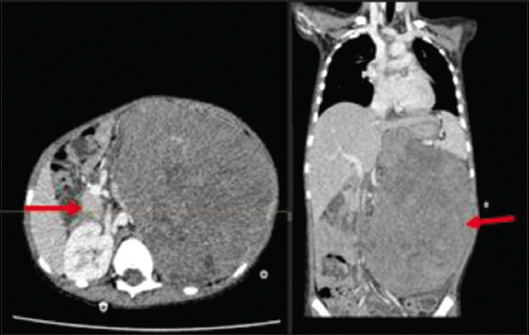

Case description: A previously healthy 5-year-old boy with no significant past medical or surgical history presented to the clinic with gradually worsening abdominal distension associated with occasional abdominal pain, gross hematuria, and lethargy for four months. Diagnostic investigations showed an 18-cm left-sided metastatic (pulmonary) renal tumor (Wilms), which was deemed unresectable on imaging. Treatment was planned according to the SIOP-RTSG protocol. However, he became hemodynamically and vitally unstable with acute, sudden distension of the abdomen on the left side after the first cycle of chemotherapy. Imaging showed active bleeding from an inferior branch of the left renal artery. Selective angioembolization was done, and chemotherapy was reinitiated with a patent left main renal artery. Following the fourth cycle of chemotherapy, he developed hemodynamic instability and abdominal pain; imaging revealed the resolution of pulmonary nodules and bleeding from the left renal artery (main); this was again embolized, and the patient was stabilized. The patient was operated on after optimization, and a complete resection of the mass was done with negative margins. On six months follow-up, he is well.

Practical implications: To the best of our knowledge, this is the first case where angioembolization has been done in conjunction with neoadjuvant chemotherapy to downsize a Wilms tumor to achieve favorable outcomes. Continued research efforts are necessary to optimize strategies and improve the prognosis for pediatric patients, and this case is one of the prime examples.